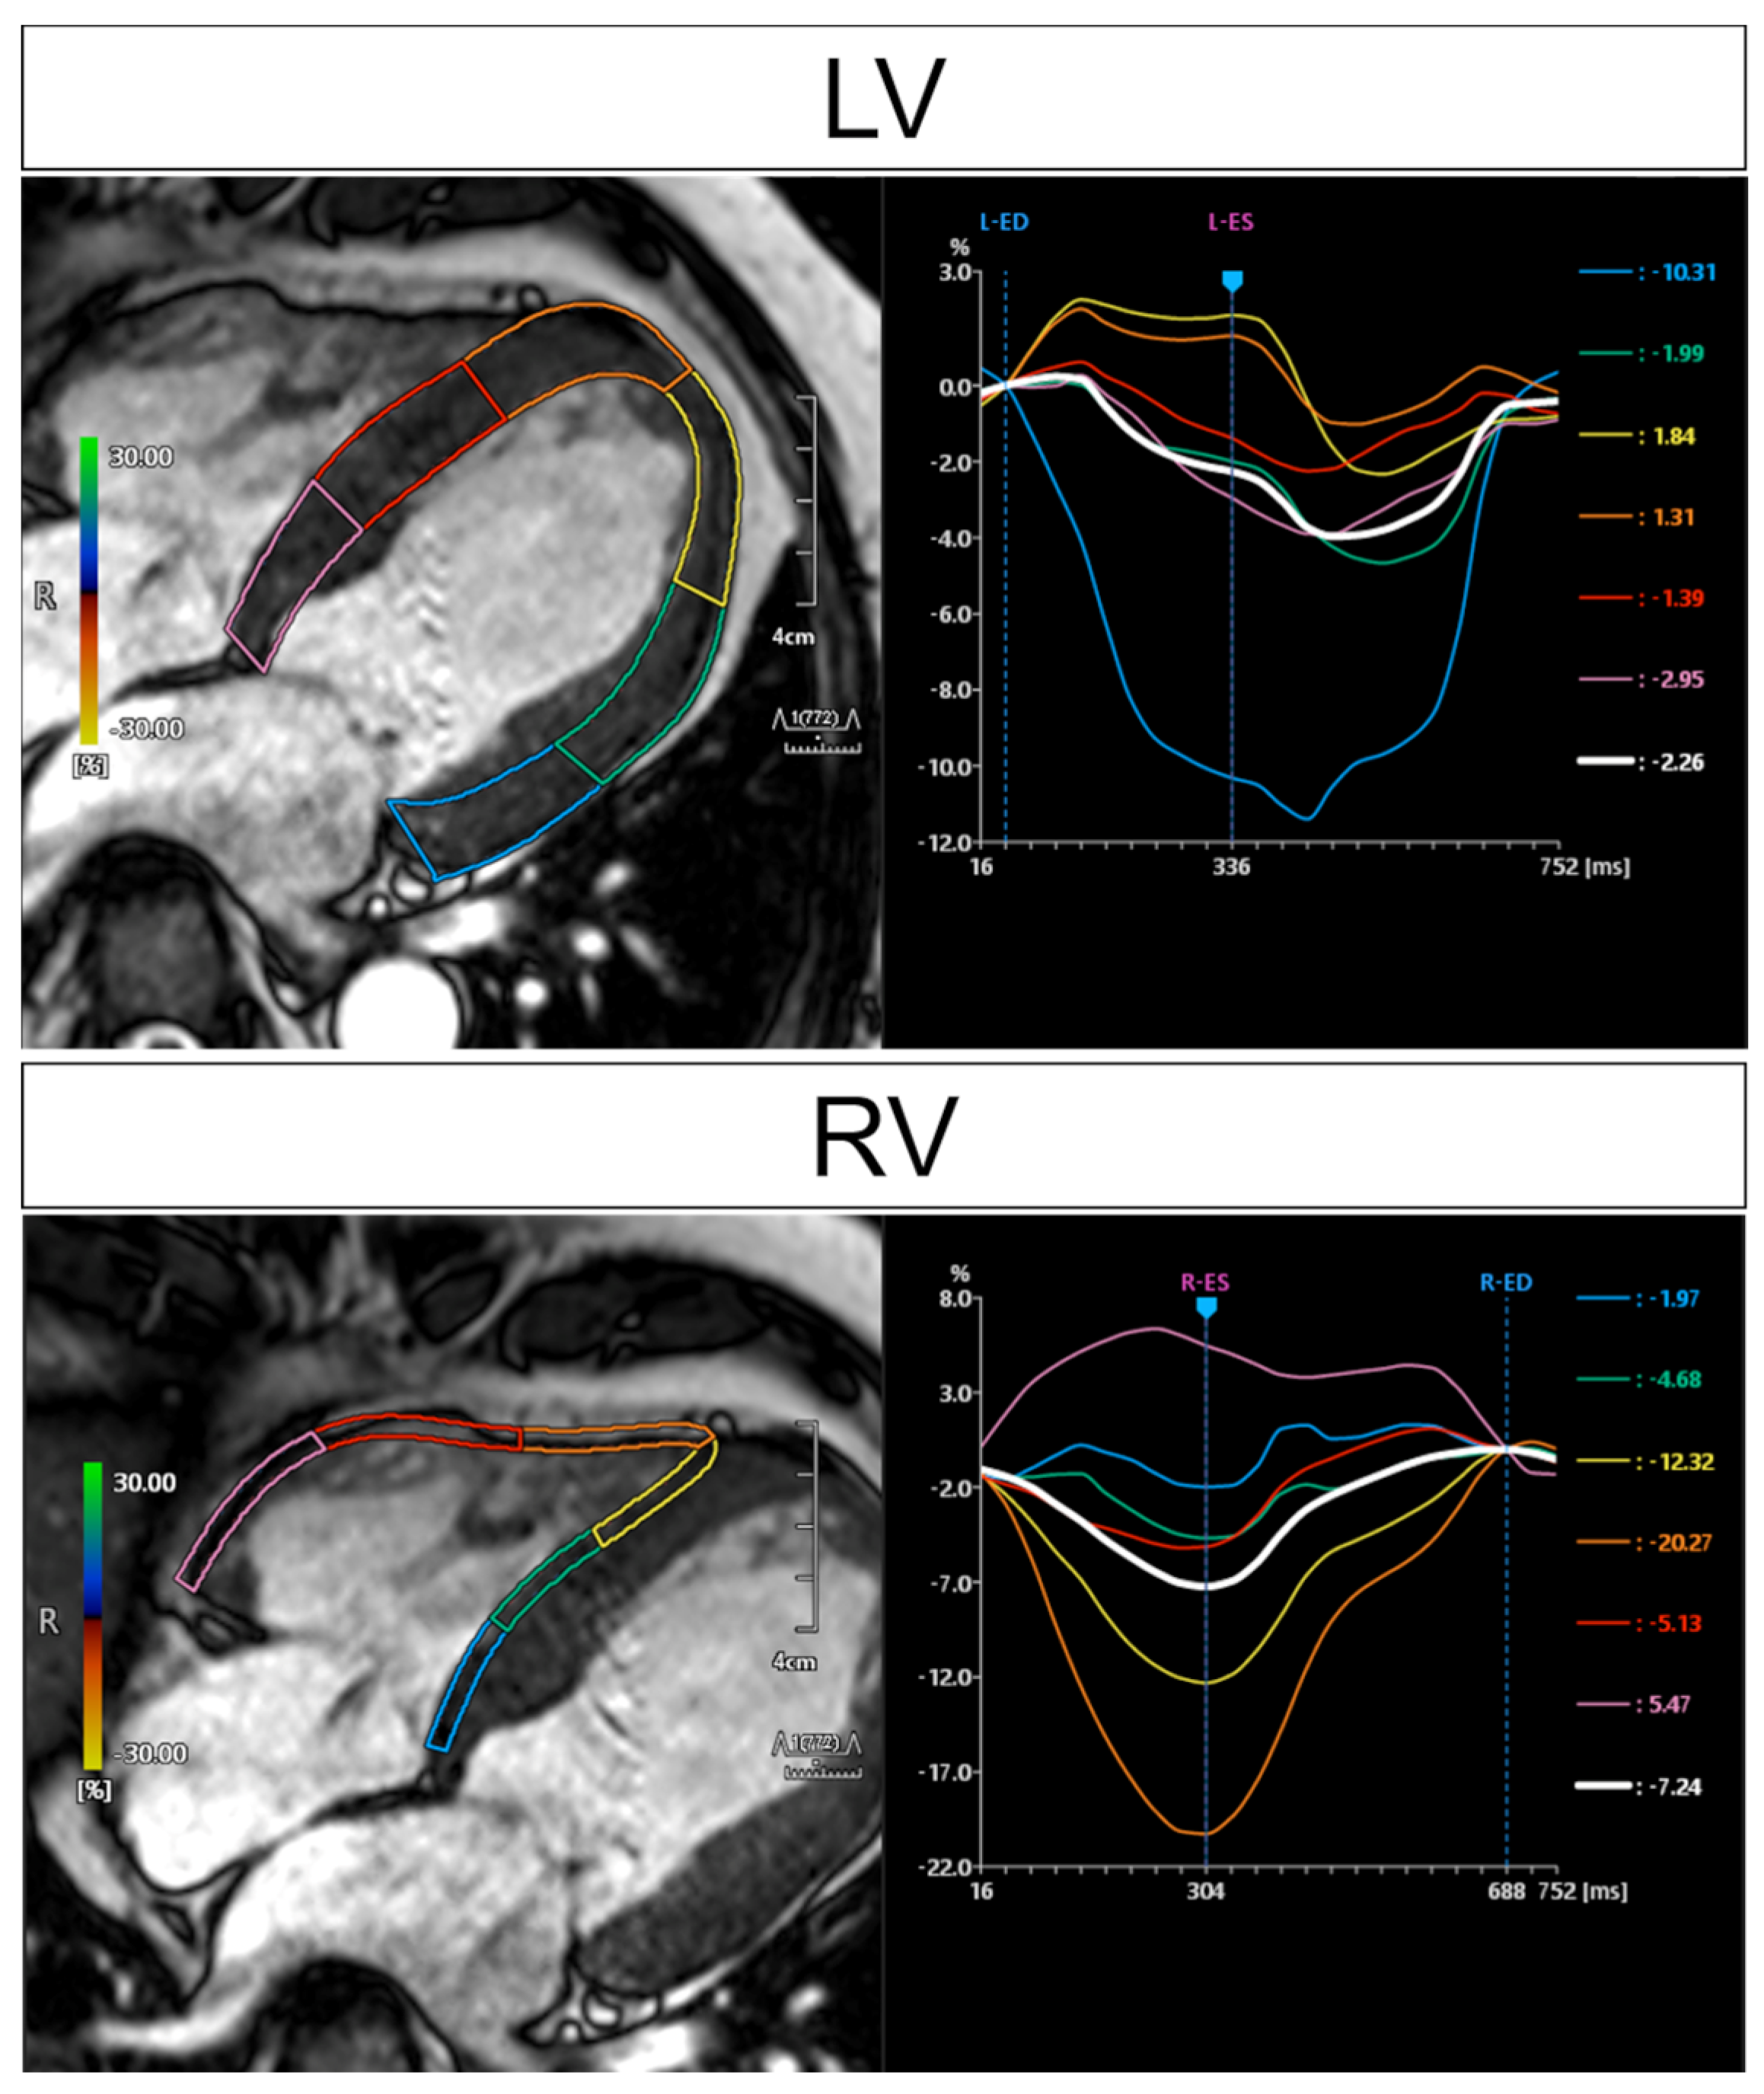

- Dabir, D.; Meyer, D.; Kuetting, D.; Luetkens, J.; Homsi, R.; Pizarro, C.; Nadal, J.; Thomas, D. Diagnostic Value of Cardiac Magnetic Resonance Strain Analysis for Detection of Cardiac Sarcoidosis. Rofo 2018, 190, 712–721. [Google Scholar] [CrossRef] [Green Version]

- Velangi, P.S.; Chen, K.A.; Kazmirczak, F.; Okasha, O.; von Wald, L.; Roukoz, H.; Farzaneh-Far, A.; Markowitz, J.; Nijjar, P.S.; Bhargava, M.; et al. Right Ventricular Abnormalities on Cardiovascular Magnetic Resonance Imaging in Patients with Sarcoidosis. JACC Cardiovasc. Imaging 2020, 13, 1395–1405. [Google Scholar] [CrossRef] [PubMed]